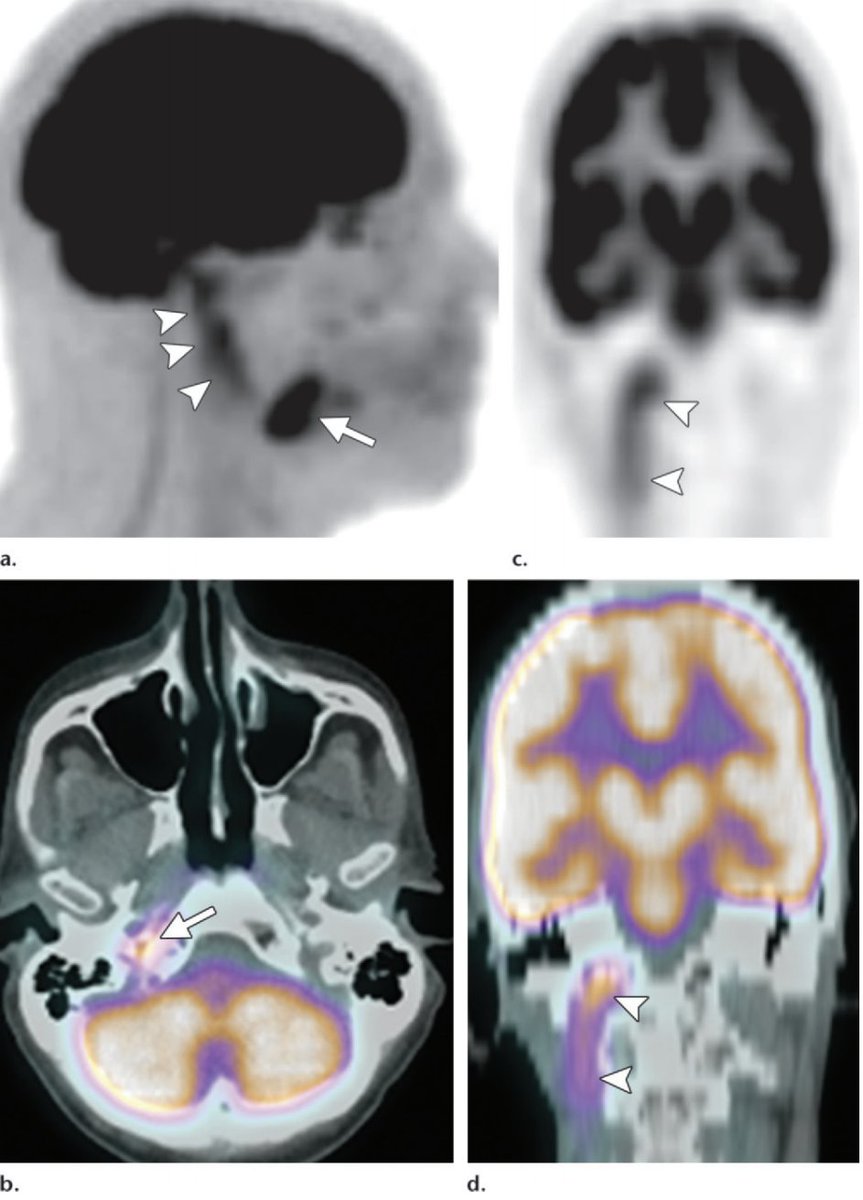

The facial nerve enters the skull at the stylomastoid foramen. There's a tiny pad of fat there!

Normal right fat pad and perineural spread of parotid mucoepidermoid cancer on the left: